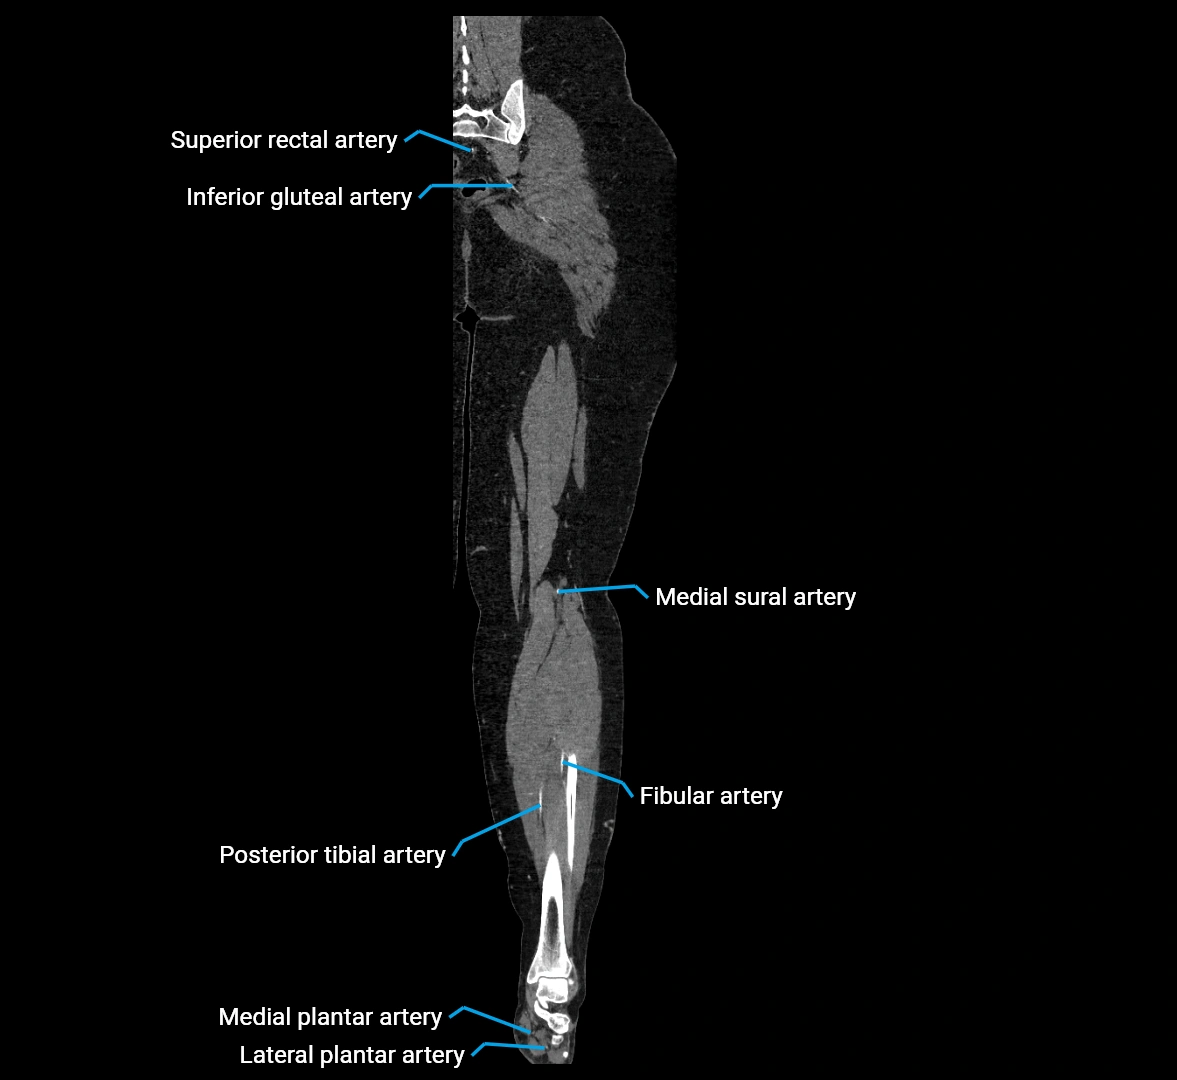

CT images

image